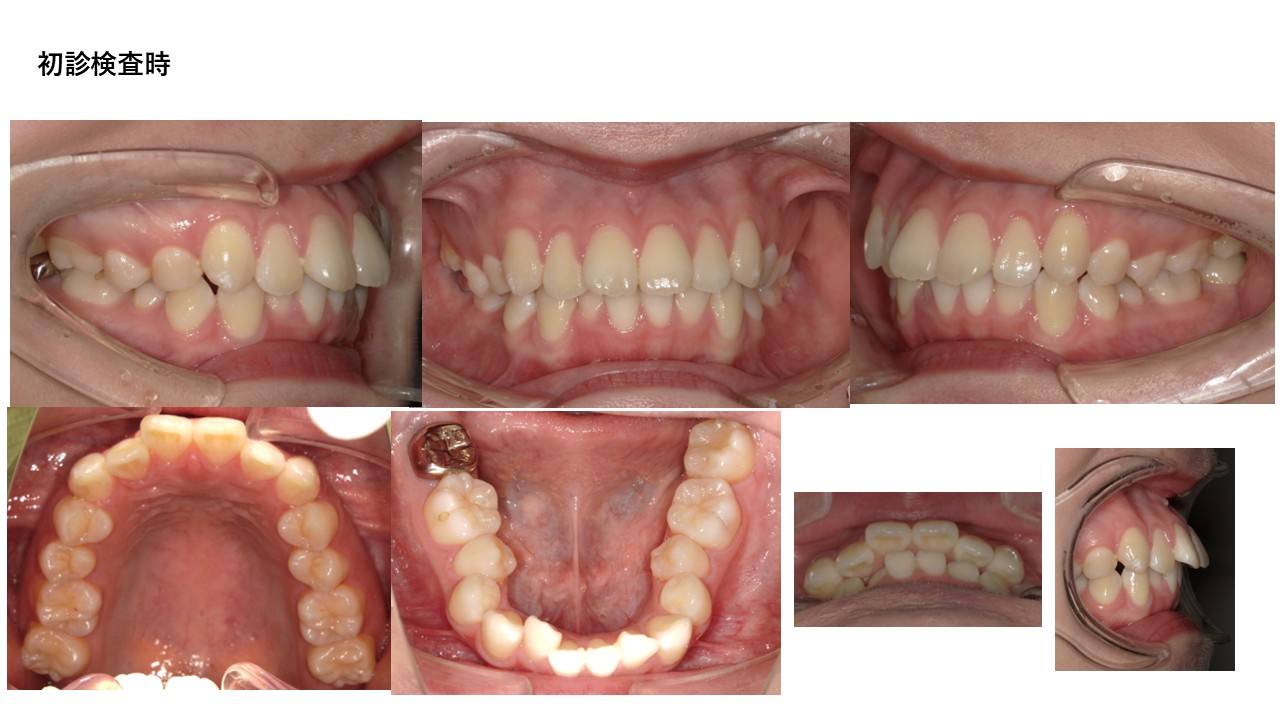

表側ワイヤー矯正

| 主訴 | 叢生、前突 |

|---|---|

| 年齢 | 20代 |

| 治療期間 | 2年4ヶ月 |

| 治療回数 | 19回 |

| 治療に用いた主な装置 | カスタムメイド型マルチブラケットタイプのデジタル矯正装置(インシグニア) |

| 治療費 | 800,000円(税別) |

| 抜歯部位 | 上下顎第一小臼歯4本 |

| リスク・副作用 |

1. 矯正装置を装着すると、不快感や痛みが生じることがあります。通常、数日〜1週間ほどで痛みが消失し、慣れることが多いです。 2. 歯の動き方には個人差があり、予想された治療期間より長引く可能性があります。 |